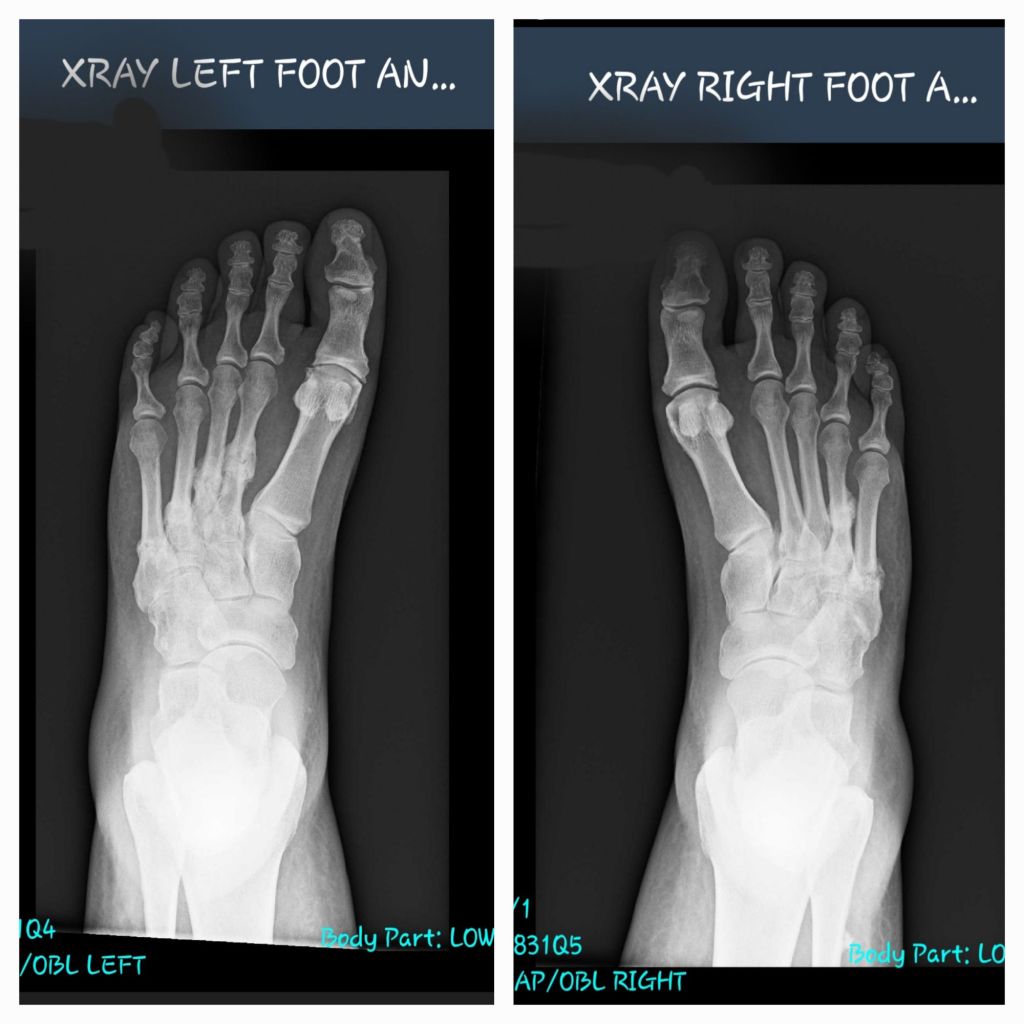

I had scans this week on my feet, which show twelve fractures across both feet.